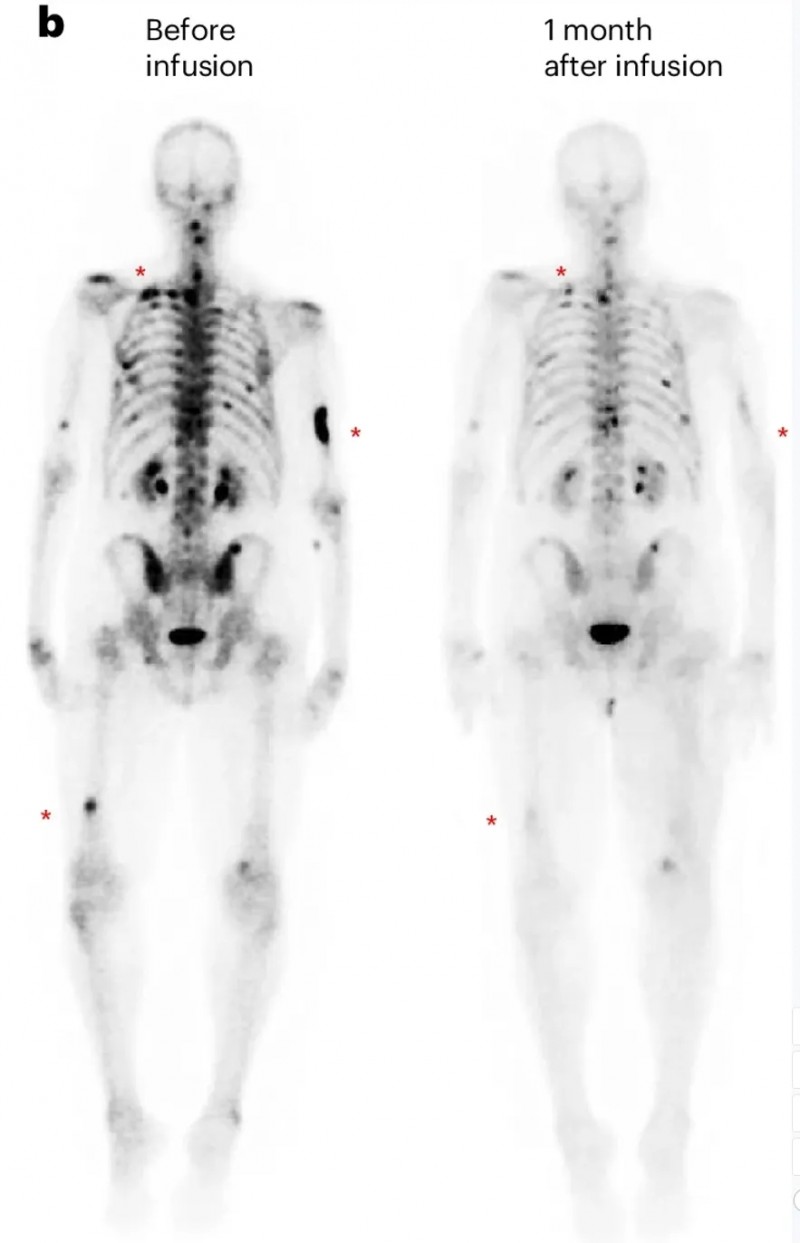

另一例为前列腺癌伴胰腺转移患者(UPN388):输注PSCA-CAR-T前后的CT复查显示,输注前病灶大小为40.2×24.8mm,输注后1个月病变完全消退、已无法测量(详见下图e);尽管因存在骨转移,RECIST评估结果为“病情稳定”,但患者软组织转移灶的放射学表现已有所改善(详见下图b)。

▲图源“Nature Medicine”,版权归原作者所有,如无意中侵犯了知识产权,请联系我们删除